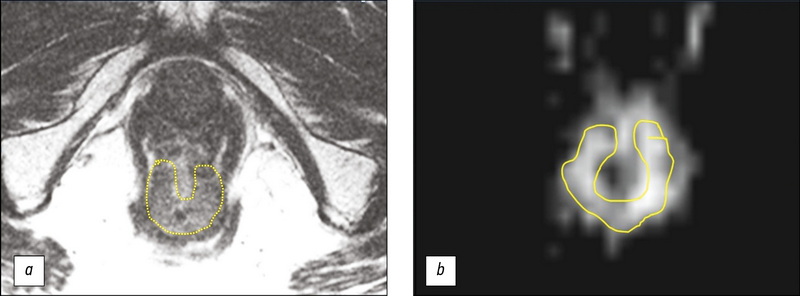

МРТ-оценка результата неоадъювантной химиолучевой терапии у больной раком прямой кишки, дополненная текстурным анализом Т2-ВИ опухоли (клинический случай)

Аннотация

В работе представлен клинический случай использования стратегии активного динамического наблюдения (watch & wait) у 73-летней больной раком нижнеампулярного отдела прямой кишки с хорошим ответом на неоадъювантную химиолучевую терапию. После трёх лет регулярного наблюдения, включающего пальцевое ректальное исследование, ректоскопию и магнитно-резонансную томографию (МРТ), указывавших на отсутствие прогрессирования опухоли, были получены результаты позитронно-эмиссионной томографии с 18F-фтордезоксиглюкозой, совмещённой с компьютерной томографией, выявившей в нижнеампулярном отделе прямой кишки участок гиперметаболической активности (SUVmax 27,1), в связи с чем было принято решение о проведении хирургического лечения. При обсуждении вопроса об объёме операции были учтены данные МРТ, дополненные результатами текстурного анализа Т2-ВИ, подтвердившие отсутствие прогрессирования. Пациентке было проведено органосохраняющее лечение в объёме трансанальной резекции опухоли. Патоморфологическое исследование операционного препарата установило воспалительные изменения в стенке кишки и отсутствие опухоли. Данный случай демонстрирует эффективность стандартного объёма обследования при использовании стратегии watch & wait и возможность использования текстурного анализа Т2-ВИ для повышения надежности МРТ-оценки ответа опухоли на химиолучевую терапию.